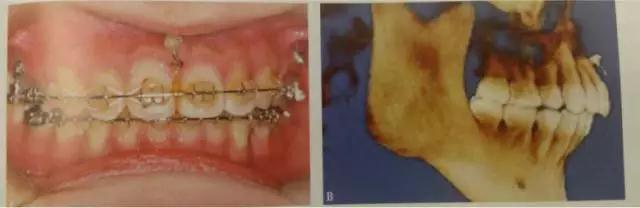

這是臨床上常見的應(yīng)用方式,多用于需要強(qiáng)支抗內(nèi)收前牙,常種植于第二前磨牙與第一磨牙、第一磨牙與第二磨牙之間,應(yīng)根據(jù)X線片觀察牙根間距離和鄰近解剖結(jié)構(gòu)確定具體部位,采用微種植體一方面可以獲得支抗以盡可能內(nèi)收前牙,另一方面可整體內(nèi)收6個(gè)前牙而不擔(dān)心支抗問題,節(jié)省了調(diào)節(jié)時(shí)間。